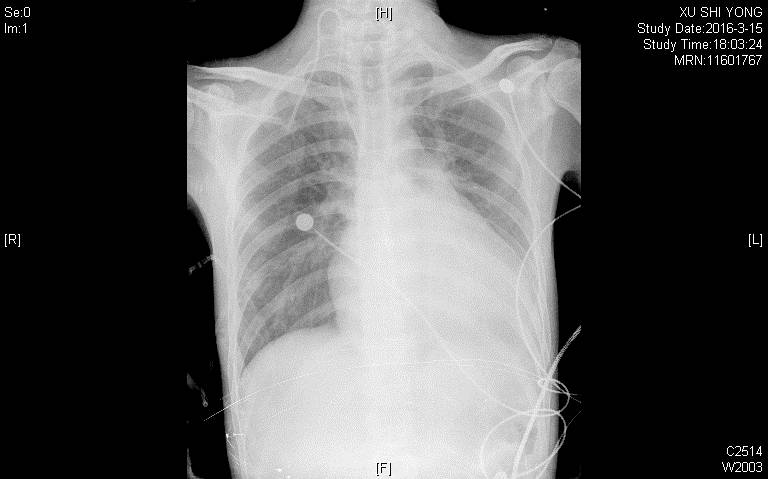

胸片:两肺淤血; 主动脉结不宽; 肺动脉段饱满; 心影增大,左心增大为主。